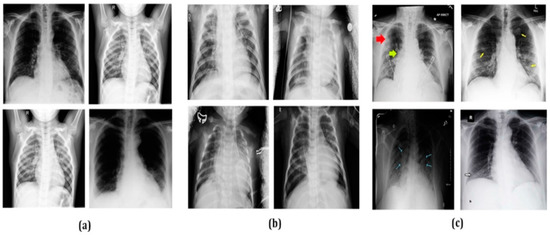

The second dataset [68] used in this study is Extensive COVID-19 X-ray and CT scan images and contains 5863 data values. The third dataset [69] provided by Mendeley Data consists of 16,490 images of both X-ray and CT scan images. Sample X-ray images and CT scan images acquired from such three benchmark imagery datasets [66,67,68,69] are displayed in Figure 1 and Figure 2 respectively.

Figure 1.

Sample X-ray images of chests of 12 patients: (a) normal chests, (b) chests with pneumonia, and (c) chests infected by COVID-19.